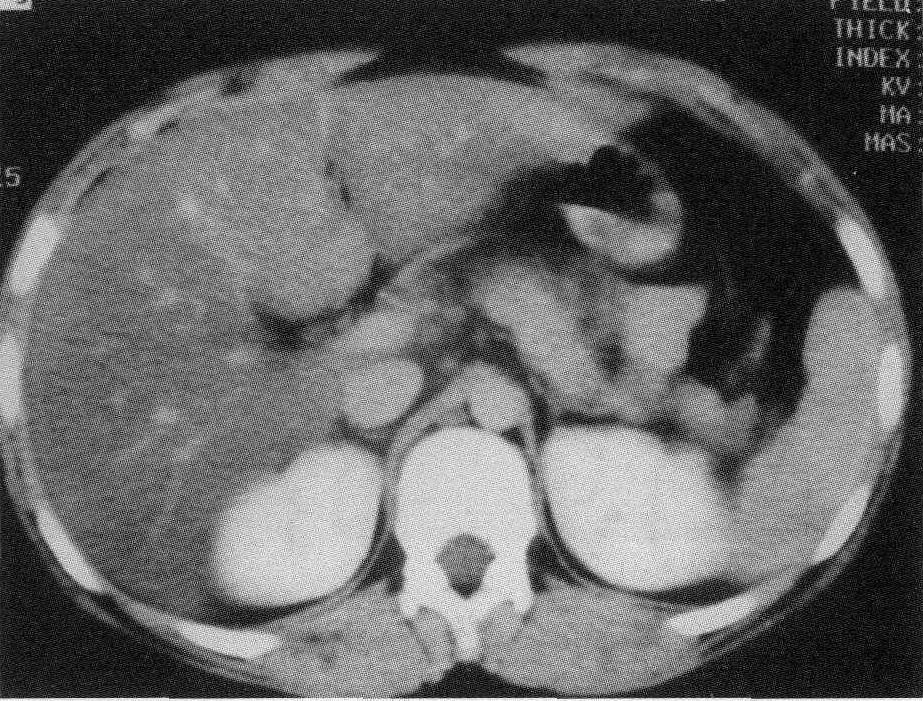

因为胰腺这玩意儿,位置非常隐蔽,藏在胃后面,被十二指肠、脾脏和肝脏等器官包围住了。

而我们一般去医院体检的项目,像超声、平扫 CT 等等这些,很难发现早期胰腺癌的特征。

当然,增强 CT 或者是增强核磁共振,能把胰腺看得更清楚些。

不过后来他在整理导师的病例资料时发现,在确诊十个月前,导师就曾做过一次平扫 CT 。

虽然当时没发现什么苗头,但带着结论回过头来分析,就能隐约看到到胰腺那里有病变的迹象。

在这样一个契机下,曹凯就想,既然人眼很难识别到平扫 CT 图像里,早期胰腺癌病变的迹象,那不如借助 AI 帮医生先筛查一遍。